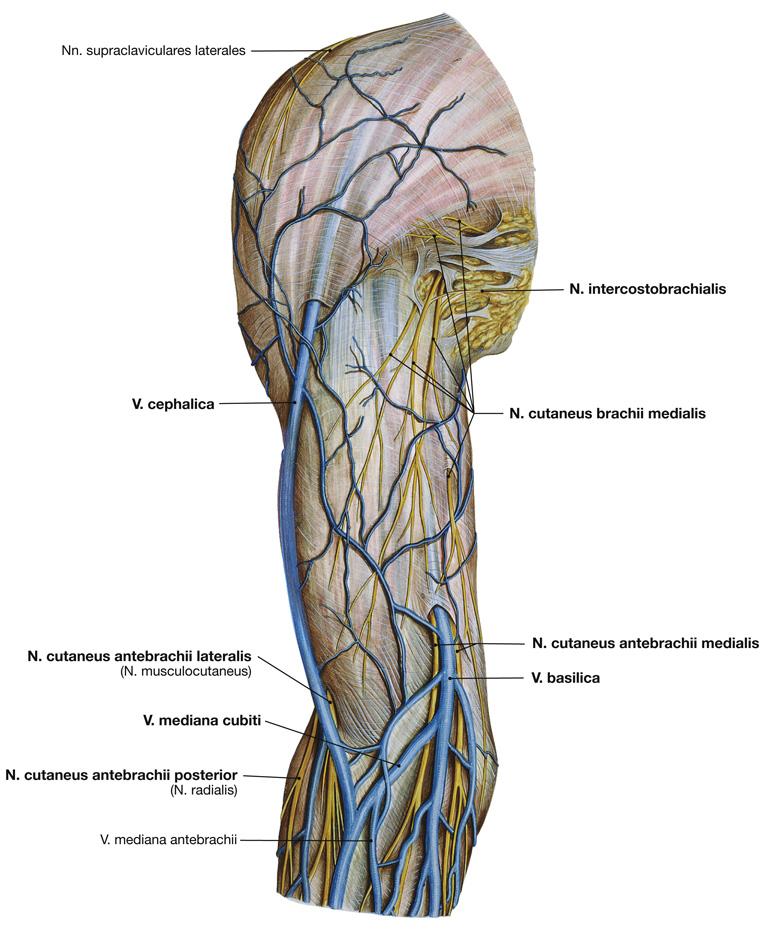

Fig 3.33: Oppervlakkige aders van de arm

|